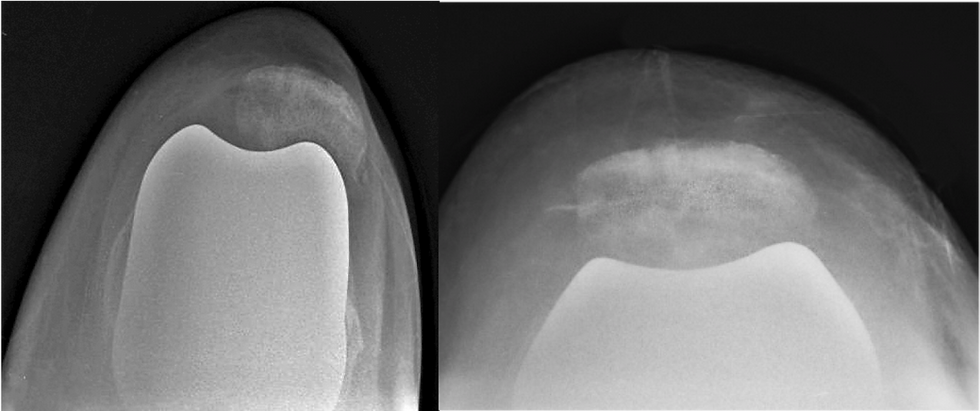

La radiografia assiale di rotula, evidenzia che la rotula è dislocata verso l’esterno (sublussazione). Si noti come nella rotula, si sia creato un solco nel suo versante articolare

Confronto fra il rx assiale di rotula prima dell’intervento (sin) e dopo (dx)

Dopo l’intervento correttivo e di protesizzazione della rotula, questa appare ben centrata rispetto alla componente dello scudo femorale.